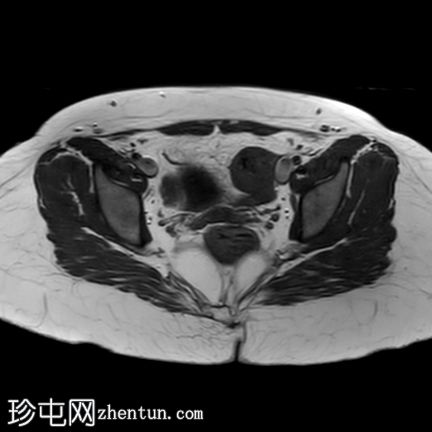

轴位

T2加权像

轴位T2加权像

盆腔两侧可见两个残角,位于双侧卵巢尾侧。可见一条水平带连接两个残角。左侧残角呈腔状,右侧残角呈非腔状。

可见宫颈阴道发育不全,从两个残角延伸出少量发育不良的宫颈组织带。

双侧卵巢功能正常,可见卵泡。

本病例展示了一种 Mayer-Rokitansky-Küster-Hauser 综合征 (MRKH),其特征为子宫缺失和双侧残角;左侧子宫角呈腔状,右侧子宫角呈非腔状。子宫角位于盆腔两侧,双侧卵巢尾侧,并由一条水平带连接。该病伴有宫颈阴道发育不全。

MRKH 患者常常被误认为完全没有子宫。有时,患者存在残角,残角内可见管腔内积血或子宫腺肌症,提示子宫内膜功能尚存。